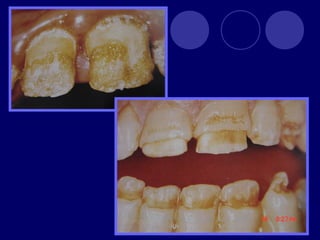

AMELOGENESIS IMPERFECTA  Hipoplásico: Zonas ausentes de esmalte  Afecta más a caras vestibulares  Esmalte: blanco amarillento y marrón claro, consistencia dura, fosas y surcos oscuras, delgado  Hipocalcificado:  Cualitativo  Esmalte frágil, fácil de desprender  Rx: falta de contacto entre dentina, esmalte  Hipomaduro:  Disminución en el contenido mineral  Esmalte blando y rugoso, veteado de blanco a marrón (esmalte en copos de nieve)  Más frecuente en caras vestibulares y dientes superiores

DISPLASIA AMBIENTAL DEL ESMALTE HIPOPLASIA POR INGESTA DE FLÚOR: fluorosis, manchas opacas, esmalte sin brillo(leve=lechoso, graves=amarillo/café) .